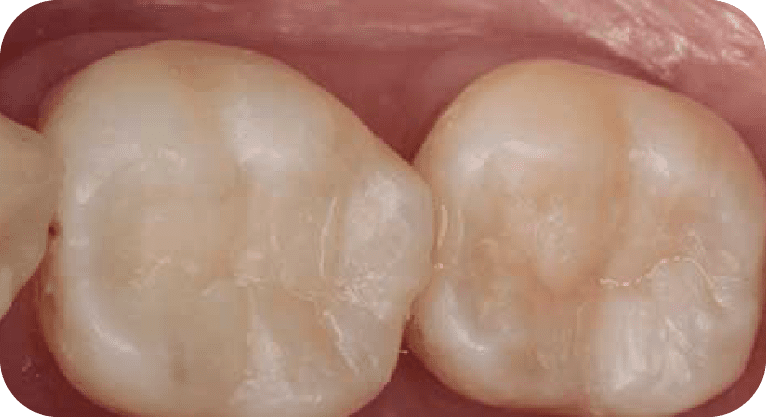

Paciente masculino, “32” años

Tratamiento: Tratamiento de conducto

El paciente requería tratamiento en dos dientes con pulpitis irreversible. Se realizaron endodoncias con microscopio y se restauraron las piezas según su daño, eliminando el dolor y evitando extracciones.

Paciente masculino, “25” años

Tratamiento: Tratamiento de conducto

El paciente presentaba dolor en dos molares por caries profundas. Se realizó endodoncia en ambas piezas, desinfectando y sellando los conductos, seguido de coronas de zirconio para restaurar su función.